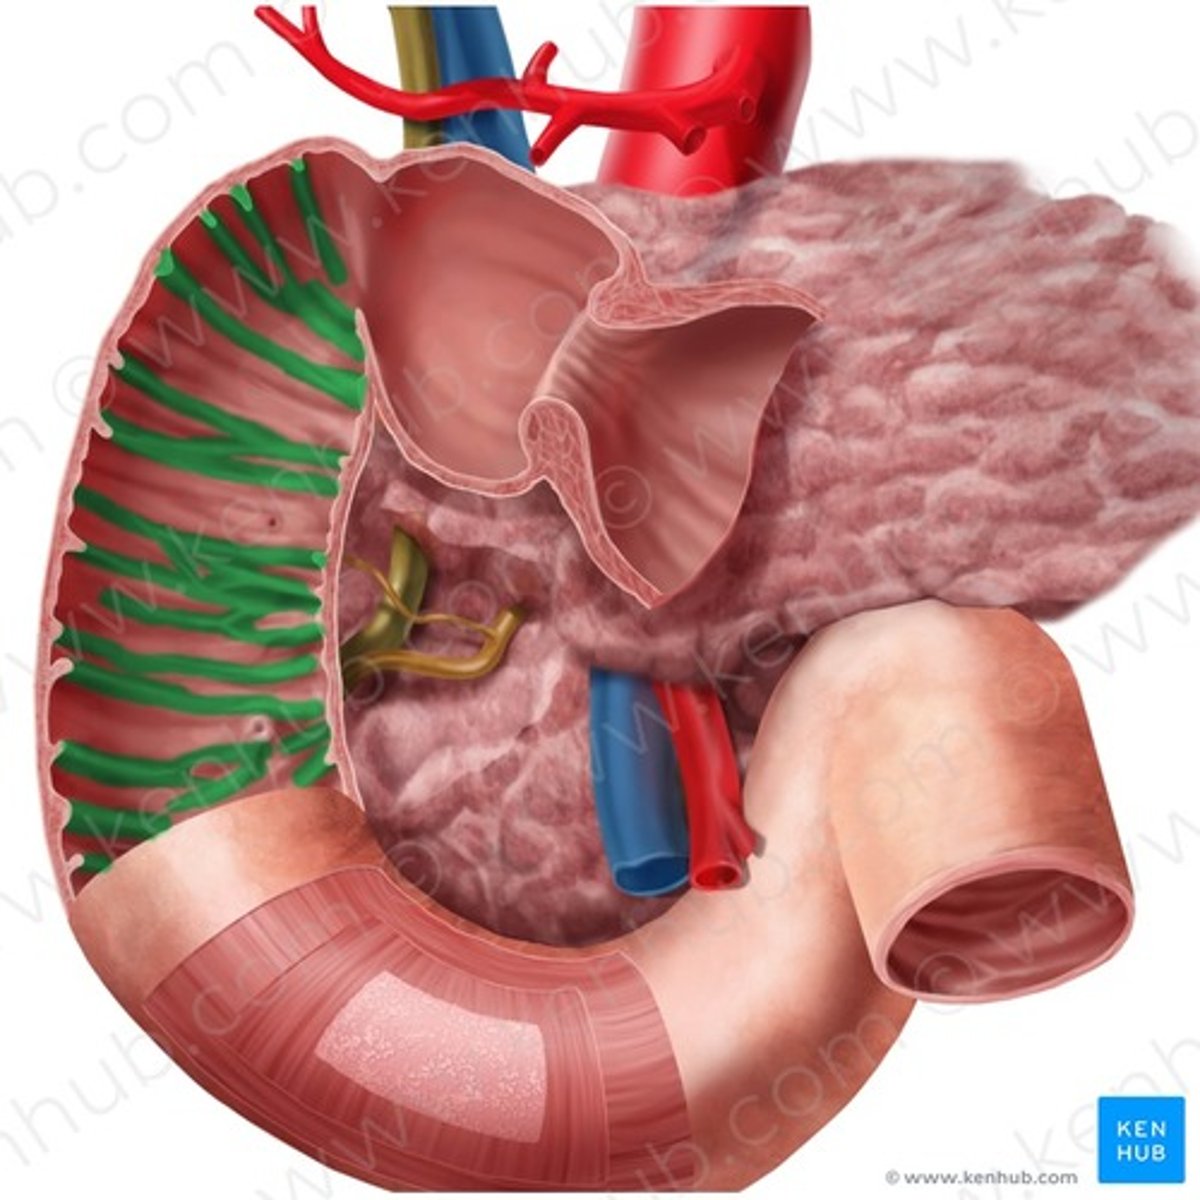

duodenum

major duodenal papilla

opening of ampulla into duodenum

circular folds (duodenum)

head (of pancreas)

main pancreatic duct

accessory pancreatic duct

hepatopancreatic ampulla

pancreatic + bile duct